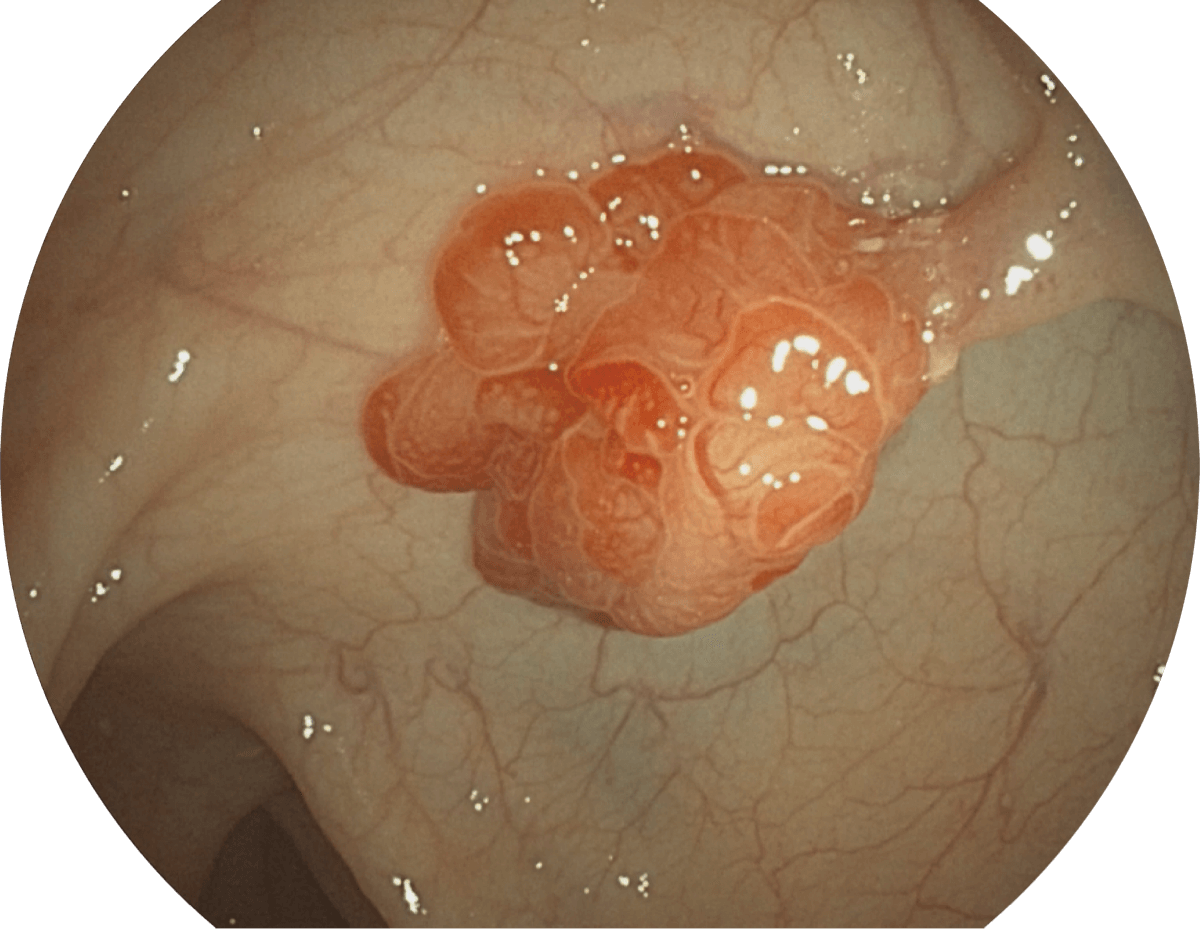

具有聚谱成像技术(SFI)及光电复合染色成像技术(VIST),可完美呈现粘膜细节及病变特征。

WL

SFI

VIST